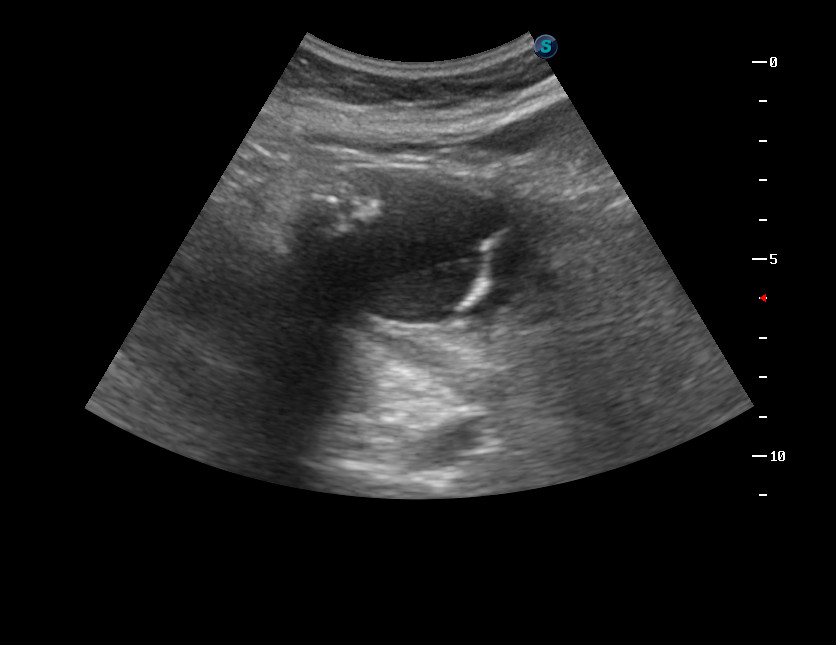

Пожилая бабушка, в левой доле печени такая ерунда.

Эхинококк? - кто что думает?

Учитывая плотную стенку, эхогенный осадок и изогнутые линейные структуры,как-то ничего другого кроме эхинококка в голову не приходит.